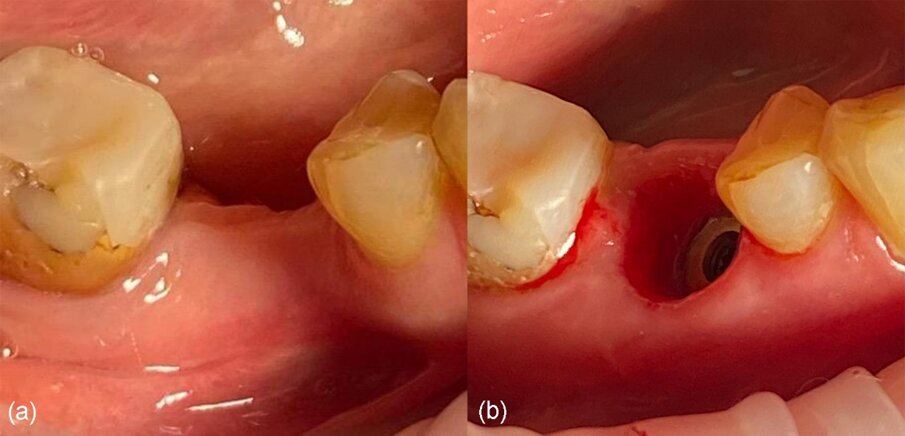

Una paziente di 51 anni di sesso femminile ha frequentato la nostra clinica cercando una riabilitazione in un sito edentulo inferiore 46. L’elemento dentale 46 è stato estratto più di 4 mesi prima della consulenza e non è stato utilizzato alcun materiale per la conservazione dell’alveolo. La paziente era una non fumatrice in buona salute, senza malattie parodontali (nessuna perdita di attacco, tasche al sondaggio e BoP). È stato eseguito un esame pre-operatorio con tomografia computerizzata a fascio conico (CBCT) nel quarto quadrante inferiore, che ha rivelato una significativa perdita ossea orizzontale nella zona edentula (Fig. 1). La densità ossea è stata classificata come tipo 2 e la distanza dal margine alveolare più coronale al canale alveolare inferiore era sufficiente per posizionare un impianto dentale (più di 10 mm) (Fig. 1). L’esame clinico ha rivelato una larghezza del tessuto cheratinizzato di più di 4 mm sulla cresta comunque sottile (Fig. 2). Il paziente è stato trattato con la tecnica del Poncho Lamina per un processo di ottimizzazione in un solo passo (Processo O.S.O.) nel sito 46. In questo caso, abbiamo selezionato e utilizzato un impianto MIS V3 (MIS Implants Technologies) e una ben documentata barriera corticale Soft Lamina 25x25 (Osteobiol by Tecnoss). L’ottimizzazione del tessuto molle è stata ottenuta con un moncone personalizzato generato tramite il sistema VPI Cervico (VP Innovato Holdings).

Fig. 2_Situazione iniziale del sito 46: a) vista occlusale, b) vista vestibolare.